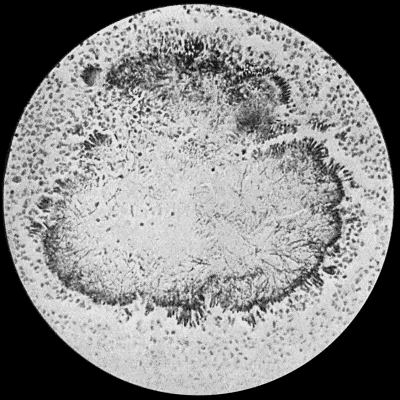

30.Colony of Actinomyces 126

Fig. 2.—Staphylococcus aureus in Pus from case of Osteomyelitis. × 1000 diam. Gram's stain.

Staphylococcus Aureus.—This is the commonest organism found in localised inflammatory and suppurative conditions. It varies greatly in its virulence, and is found in such widely different conditions as skin pustules, boils, carbuncles, and some acute inflammations of bone. As seen by the microscope it occurs in grape-like clusters, fission of the individual cells taking place irregularly (Fig. 2). When grown in artificial media, the colonies assume an orange-yellow colour—hence the name aureus. It is of high vitality and resists more prolonged exposure to high temperatures than most non-sporing bacteria. It is capable of lying latent in the tissues for long periods, for example, in the marrow of long bones, and of again becoming active and causing a fresh outbreak of suppuration. This organism is widely distributed: it is found on the skin, in the mouth, and in other situations in the body, and as it is present in the dust of the air and on all objects upon which dust has settled, it is a continual source of infection unless means are taken to exclude it from wounds.